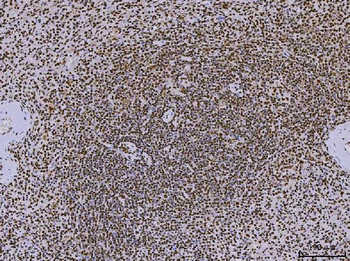

Anti-PC4/SUB1 Antibody (monoclonal, 8D9D1) [orb1184747]

FC, IF, IHC, WB

Human, Mouse, Rat

Mouse

Monoclonal

Unconjugated

10 μg, 100 μgAnti-PC4/SUB1 Antibody (monoclonal, 6B5B10) [orb1145777]